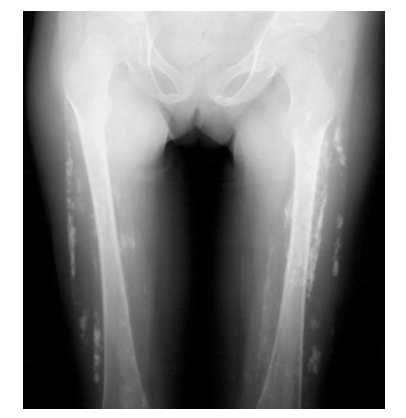

What is this?

Extensive soft-tissue calcifications are noted bilaterally in

the lower extremities of this patient with dermatomyositis.